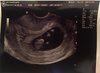

gratulacje! wstaw zdjęcie jestem ciekawa!!!Nie moge wstawic foto ...blizniaki.. Jestem w szoku

Gratulacje!!Nie moge wstawic foto ...blizniaki.. Jestem w szoku

Wow. Podwójne szczescieNie moge wstawic foto ...blizniaki.. Jestem w szoku

Gratulacje, który to tydzień?Dziś i ja byłam u lekarzaMaluszek tak się ruszał, że ciężko było zrobić zdjęcie

9 tydzień 3 dzieńGratulacje, który to tydzień?